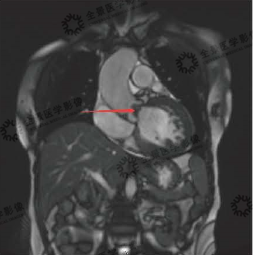

▲心脏电影序列

心脏电影示心室壁运动无明显异常,各节段运动协调,LVEF:71.7%

▲延迟强化序列

基底段-中央段间隔量、心尖段前型,间隔型、下型、侧整心肌中层可见条片状延迟强化(红色箭头)

心脏磁共振显示:非对称性肥厚型心肌病,间隔壁多发心肌纤维化,左心房大;主动脉瓣重度狭窄;二尖瓣反流。